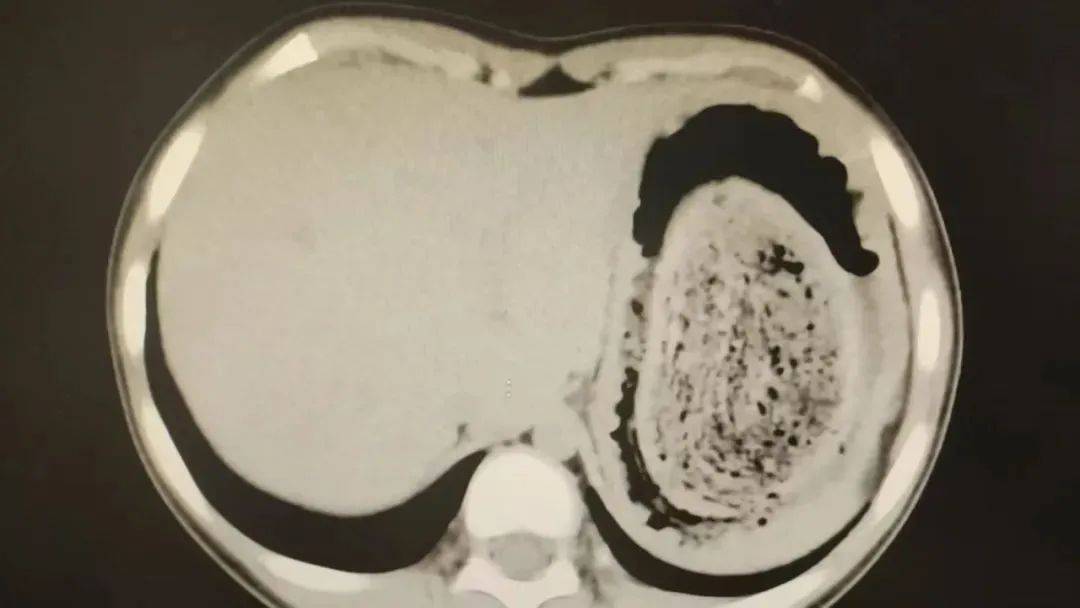

结果出来时,医生都惊呆了:小可的胃里,塞满了成团的头发,几乎占了胃容量的四分之三皇冠平台。大量不能消化的物质,在胃酸的作用下发生变性,并与食物及其他物质结合形成团块,慢慢变成坚硬的“胃石”。

为了避免用手术方式去除头发团, 陈攸涛先让小可喝可乐软化“胃石”,再通过胃镜辅助取出头发,整个过程花了十几个小时,清理出的头发装了 两大盆皇冠平台。

2024年10月,11岁女孩欢欢(化名)因腹痛难耐紧急送到医院,而就在两个月前,欢欢的父母发现她在拔自己的头发,偷偷吃掉皇冠平台。经检查,医生发现她胃腔和肠管里有大块的毛絮状结石,几乎占据整个胃部。最终,一块长38厘米、宽15厘米、厚10厘米的毛发结石被取出。